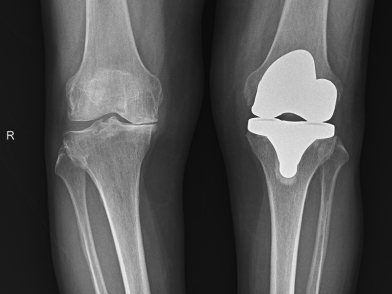

Στο τελικό στάδιο η προχωρημένη οστική καταστροφή με αυξημένο πόνο, αστάθεια και παραμόρφωση απαιτεί επανορθωτική χειρουργική επέμβαση, δηλαδή ολική αρθροπλαστική του γόνατος με εξαιρετικά αποτελέσματα.